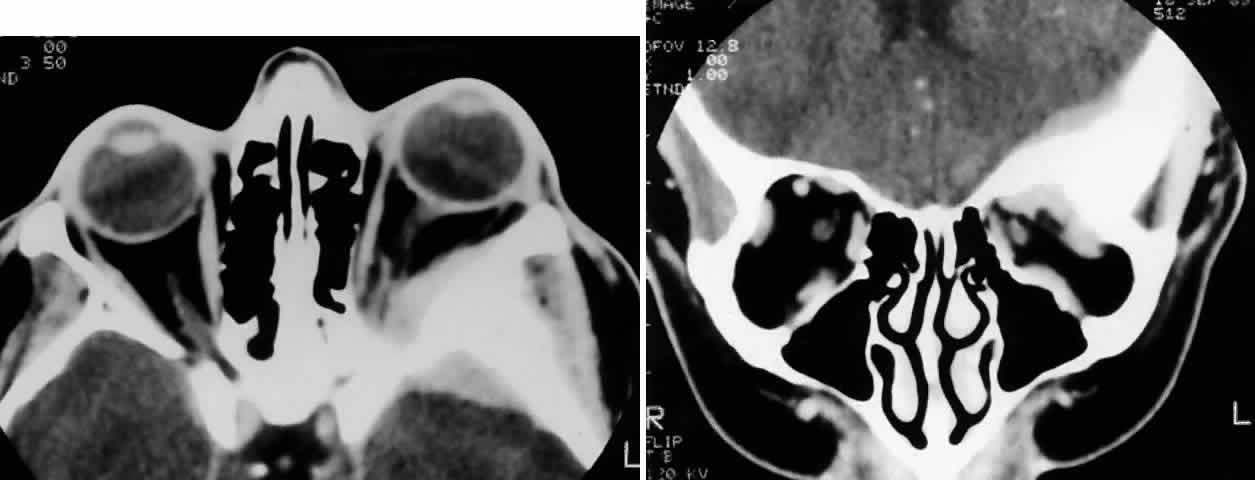

Fig. 2. A 32-year-old woman presented with a 1-month history of sinus congestion and nasal obstruction unresponsive to antibiotics. In the 1 week preceding the initial exam, the right eye became progressively more prominent and showed tearing and redness. On examination, there was mild edema of the lower lid and dysesthesia in the distribution of cranial nerve V2, and the globe was displaced 6 mm laterally and 5 mm anteriorly. There was mild limitation of abduction, chemosis, and nasal choroidal folds. An axial CT scan revealed a diffuse, destructive soft tissue mass centered in the superior nasal passage and ethmoid sinuses extending into the right orbit in contiguity with the medial rectus (A). On enhanced coronal view, the tumor was noted to involve the right maxillary antrum and to extend superiorly into the anterior cranial fossa (B). Biopsy of the sinus (C) revealed an alveolar-type rhabdomyosarcoma (muscle stain, × 320).

Fig. 3. A 73-year-old man presented with a 2-year history of infraorbital numbness and burning sensation, which had progressed to include the supraorbital region, forehead, and lower face during the past 6 months. He had been treated with radiotherapy for prostate carcinoma 7 months before orbital presentation. Examination was significant for proptosis of 2 mm and dysesthesia, including corneal numbness, in all three divisions of cranial nerve V. CT scan revealed a soft tissue mass in the inferior orbit contiguous with the inferior rectus muscle (A). The lesion extended through the infraorbital canal to involve the pterygopalatine fossa and was associated with soft tissue hanging into the upper portion of the maxillary sinus. An axial CT scan-guided aspiration biopsy was performed (B) and revealed squamous cell carcinoma. Groups of cohesive malignant squamous epithelial cells (C) were noted to have pleomorphic nuclei and abundant eosinophilic to orange cytoplasm, with no features of mucinous differentiation (H & E, × 320). (C from White VA, Rootman J: Orbital pathology. In Albert DM, Jakobiec FA (eds): Principles and Practice of Ophthalmology, Vol 4, p 2342. Philadelphia, WB Saunders, 1994.)